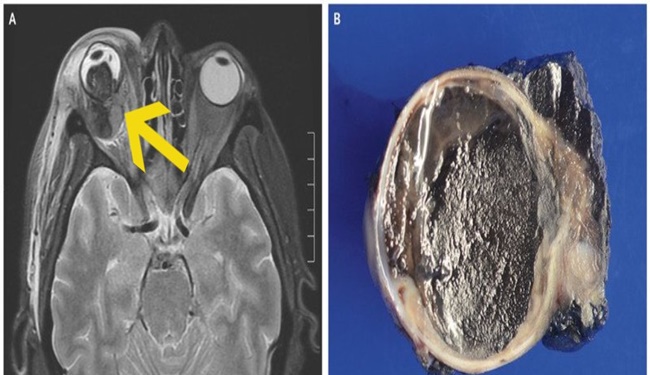

She had been blind in that eye for several years, and the report doesn’t mention if or how that had been investigated, but a magnetic resonance image below reveals what they found – and what the eye looked like when they removed it.

(Everett & Copperman, N Engl J Med, 2019)

As we mentioned, in this case the patient’s right eye was removed completely to provide her with some relief, and the 2.8 by 2.5 centimetre (around one by one inch) mass was sent for testing.